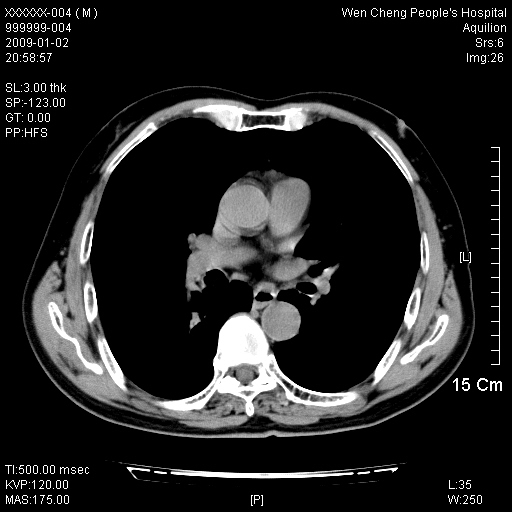

男性,73岁,有慢支病史,肿瘤系列标志物检验正常,血沉及血常规正常

支气管炎,小叶气肿,右下肺局限性炎症并轻度支气管扩张冠脉钙化。

1、慢性支气管炎。

2、右肺下叶片团状影内见扩张的含气支气管和支气管管壁增厚,其周有磨玻璃样模糊影和长毛刺。考虑周围型肺ca可能,结核不排。

3、左右冠状动脉钙化。

机化性肺炎 , 左右冠状动脉钙化。

支气管炎,小叶气肿,右下肺局限性炎症并轻度支气管扩张冠脉钙化